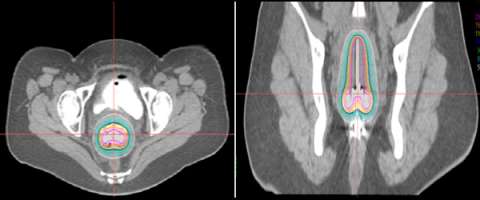

Below is an actual example of the CAPRI applicator (a 13 channel applicator) and the distribution of radiation dose that was delivered around the vaginal apex (right image axial and left image sagittal). Below to the right is a 3D depiction of the anatomy and distribution of the radiation dose (bladder in yellow, rectum in brown, applicator in purple, radiation dose in red):

CAPRI applicator

3D depiction

3D depiction of the anatomy and distribution of radiation dose.